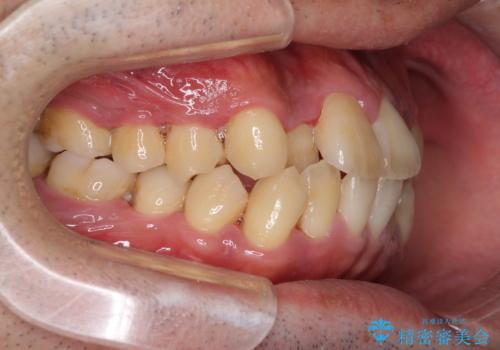

前歯のクロスバイトを改善 インビザラインによる矯正治療

- 前歯のクロスバイトを気にして来院された患者様です。

デコボコやクロスバイトが散見されたため、IPR(歯と歯の間を削る)によってスペースを獲得できるように設計し、インビザラインにより治療を行うこととしました。

今回は、ワイヤー装置を併用することなく治療を行い、トラブルなく、満足のいく歯列に整えることができました。

矯正治療の途中でホームホワイトニングを併用され、術前とは見違えるほどきれいな口元となりました。